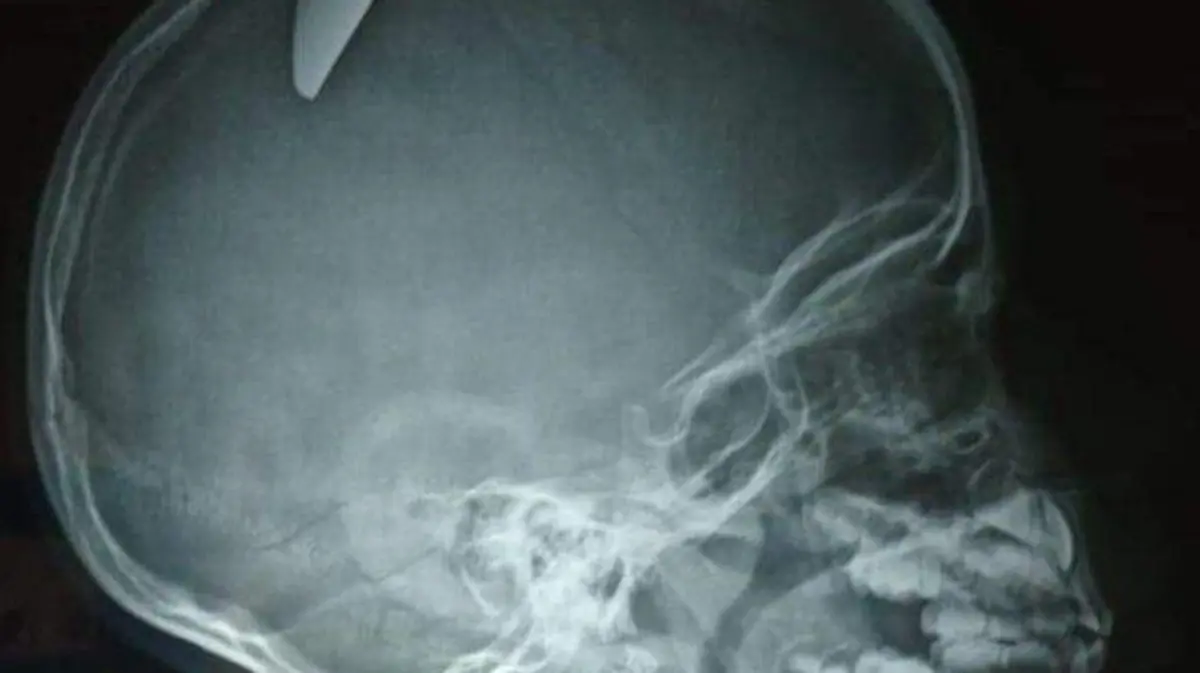

Tres mujeres fueron asesinadas durante el martes; una de ellas, de un balazo en la cabeza